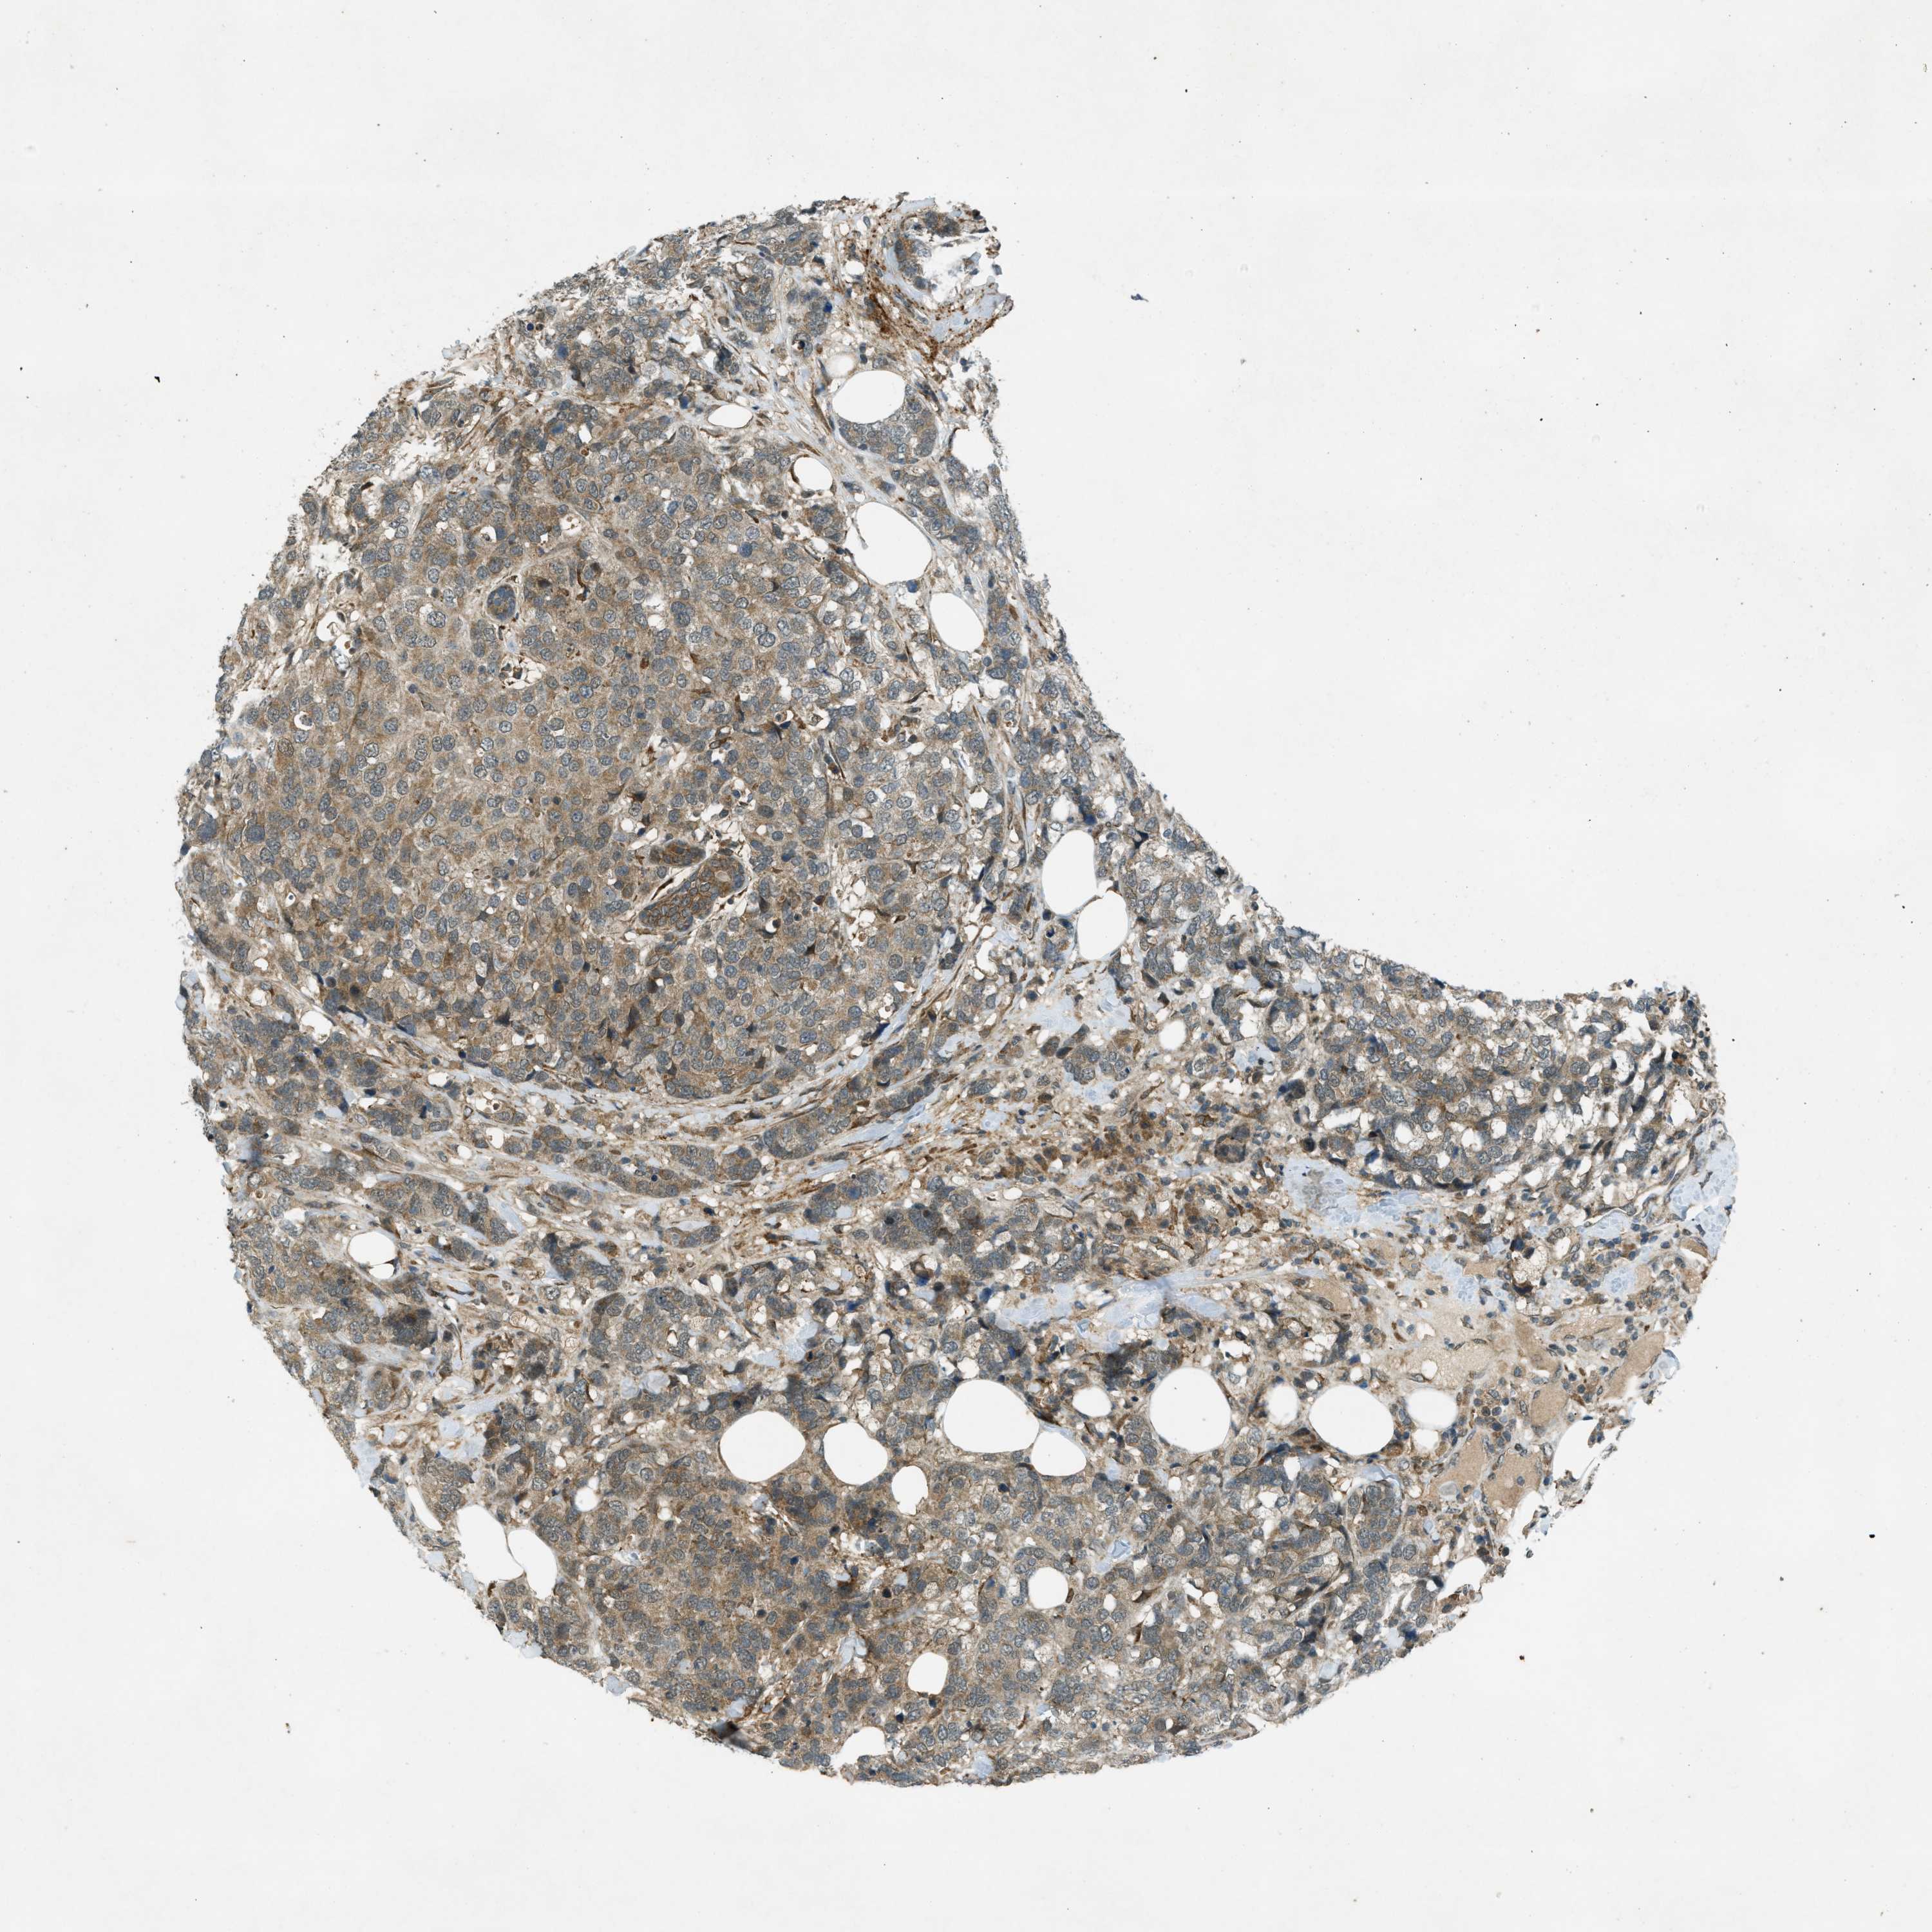

BRCA TCGA BRCA VALIDATION PROTEIN EXPRESSION

Breast cancer

Human cancer